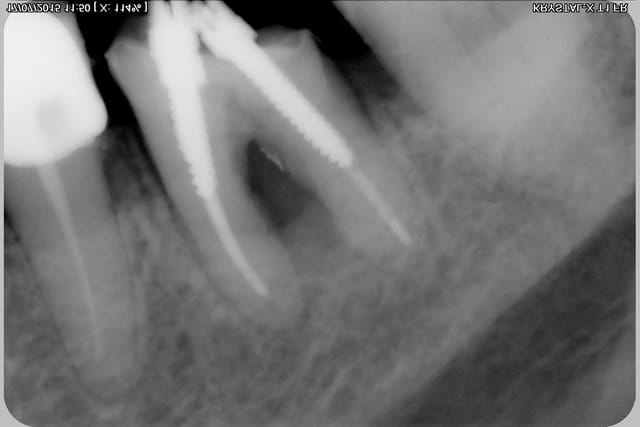

Tentative de sauvetage de 46, dépose de la ceramometal, et d'un magnifique inlay core à clavette (inter-radiculaire) (qui ne risquait pas de se barrer coincé entre les 3 parois restantes et un gros amalgame vestibulaire...(merci à la nomenclature qui rembourse ça...).

Nettoyage, curetage inter-radiculaires,lavage à l'hypochlorite, obturation (sans la digue) 3 screws post (en prévision d'une éventuelle séparation de racine)après avoir bouché la perforation à la bio dentine, recouverte d'un composite.

2 heures pour peut être rien, ou peut être pas?

sur les radios on distingue la biodentine sur la racine distale